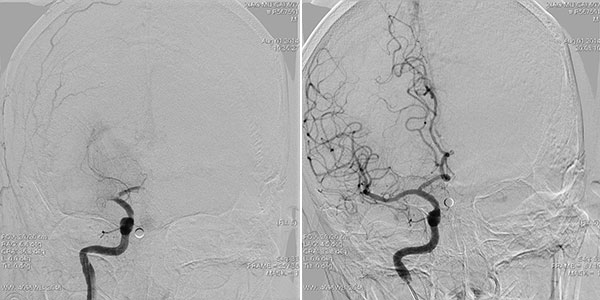

病例1 今年8月肖大伯突发烦躁不安、口角歪斜、说话不清,左侧手脚不能动弹,考虑为脑血管意外。紧急头颅CT检查,结果为脑栓塞。随后2小时在心内科和麻醉科保驾护航下,使患者安静下来,由神经内科王硕主任主刀,紧急行股动脉插管,行全脑血管造影,确定脑动脉栓塞部位(图1),立刻送入取栓装置,经过3次抓捕,终于把“原凶”栓子抓出体外(图2),阻塞脑动脉恢复血流(图3),奄奄一息的脑组织获得再生。经过6天治疗,患者痊愈走出院。

图1 取栓前,右侧大脑中动脉闭塞 图3 取栓后,右侧大脑中动脉血流再通

图2 取出2X3X4mm血栓